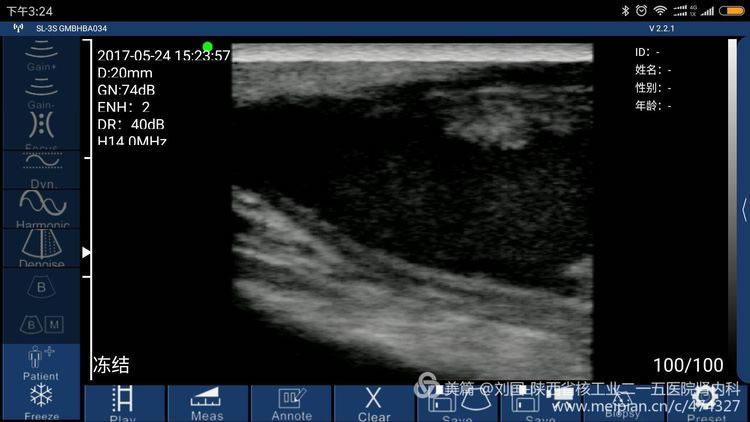

索诺星无线超声检查的头静脉情况,显示器是我的小米max。